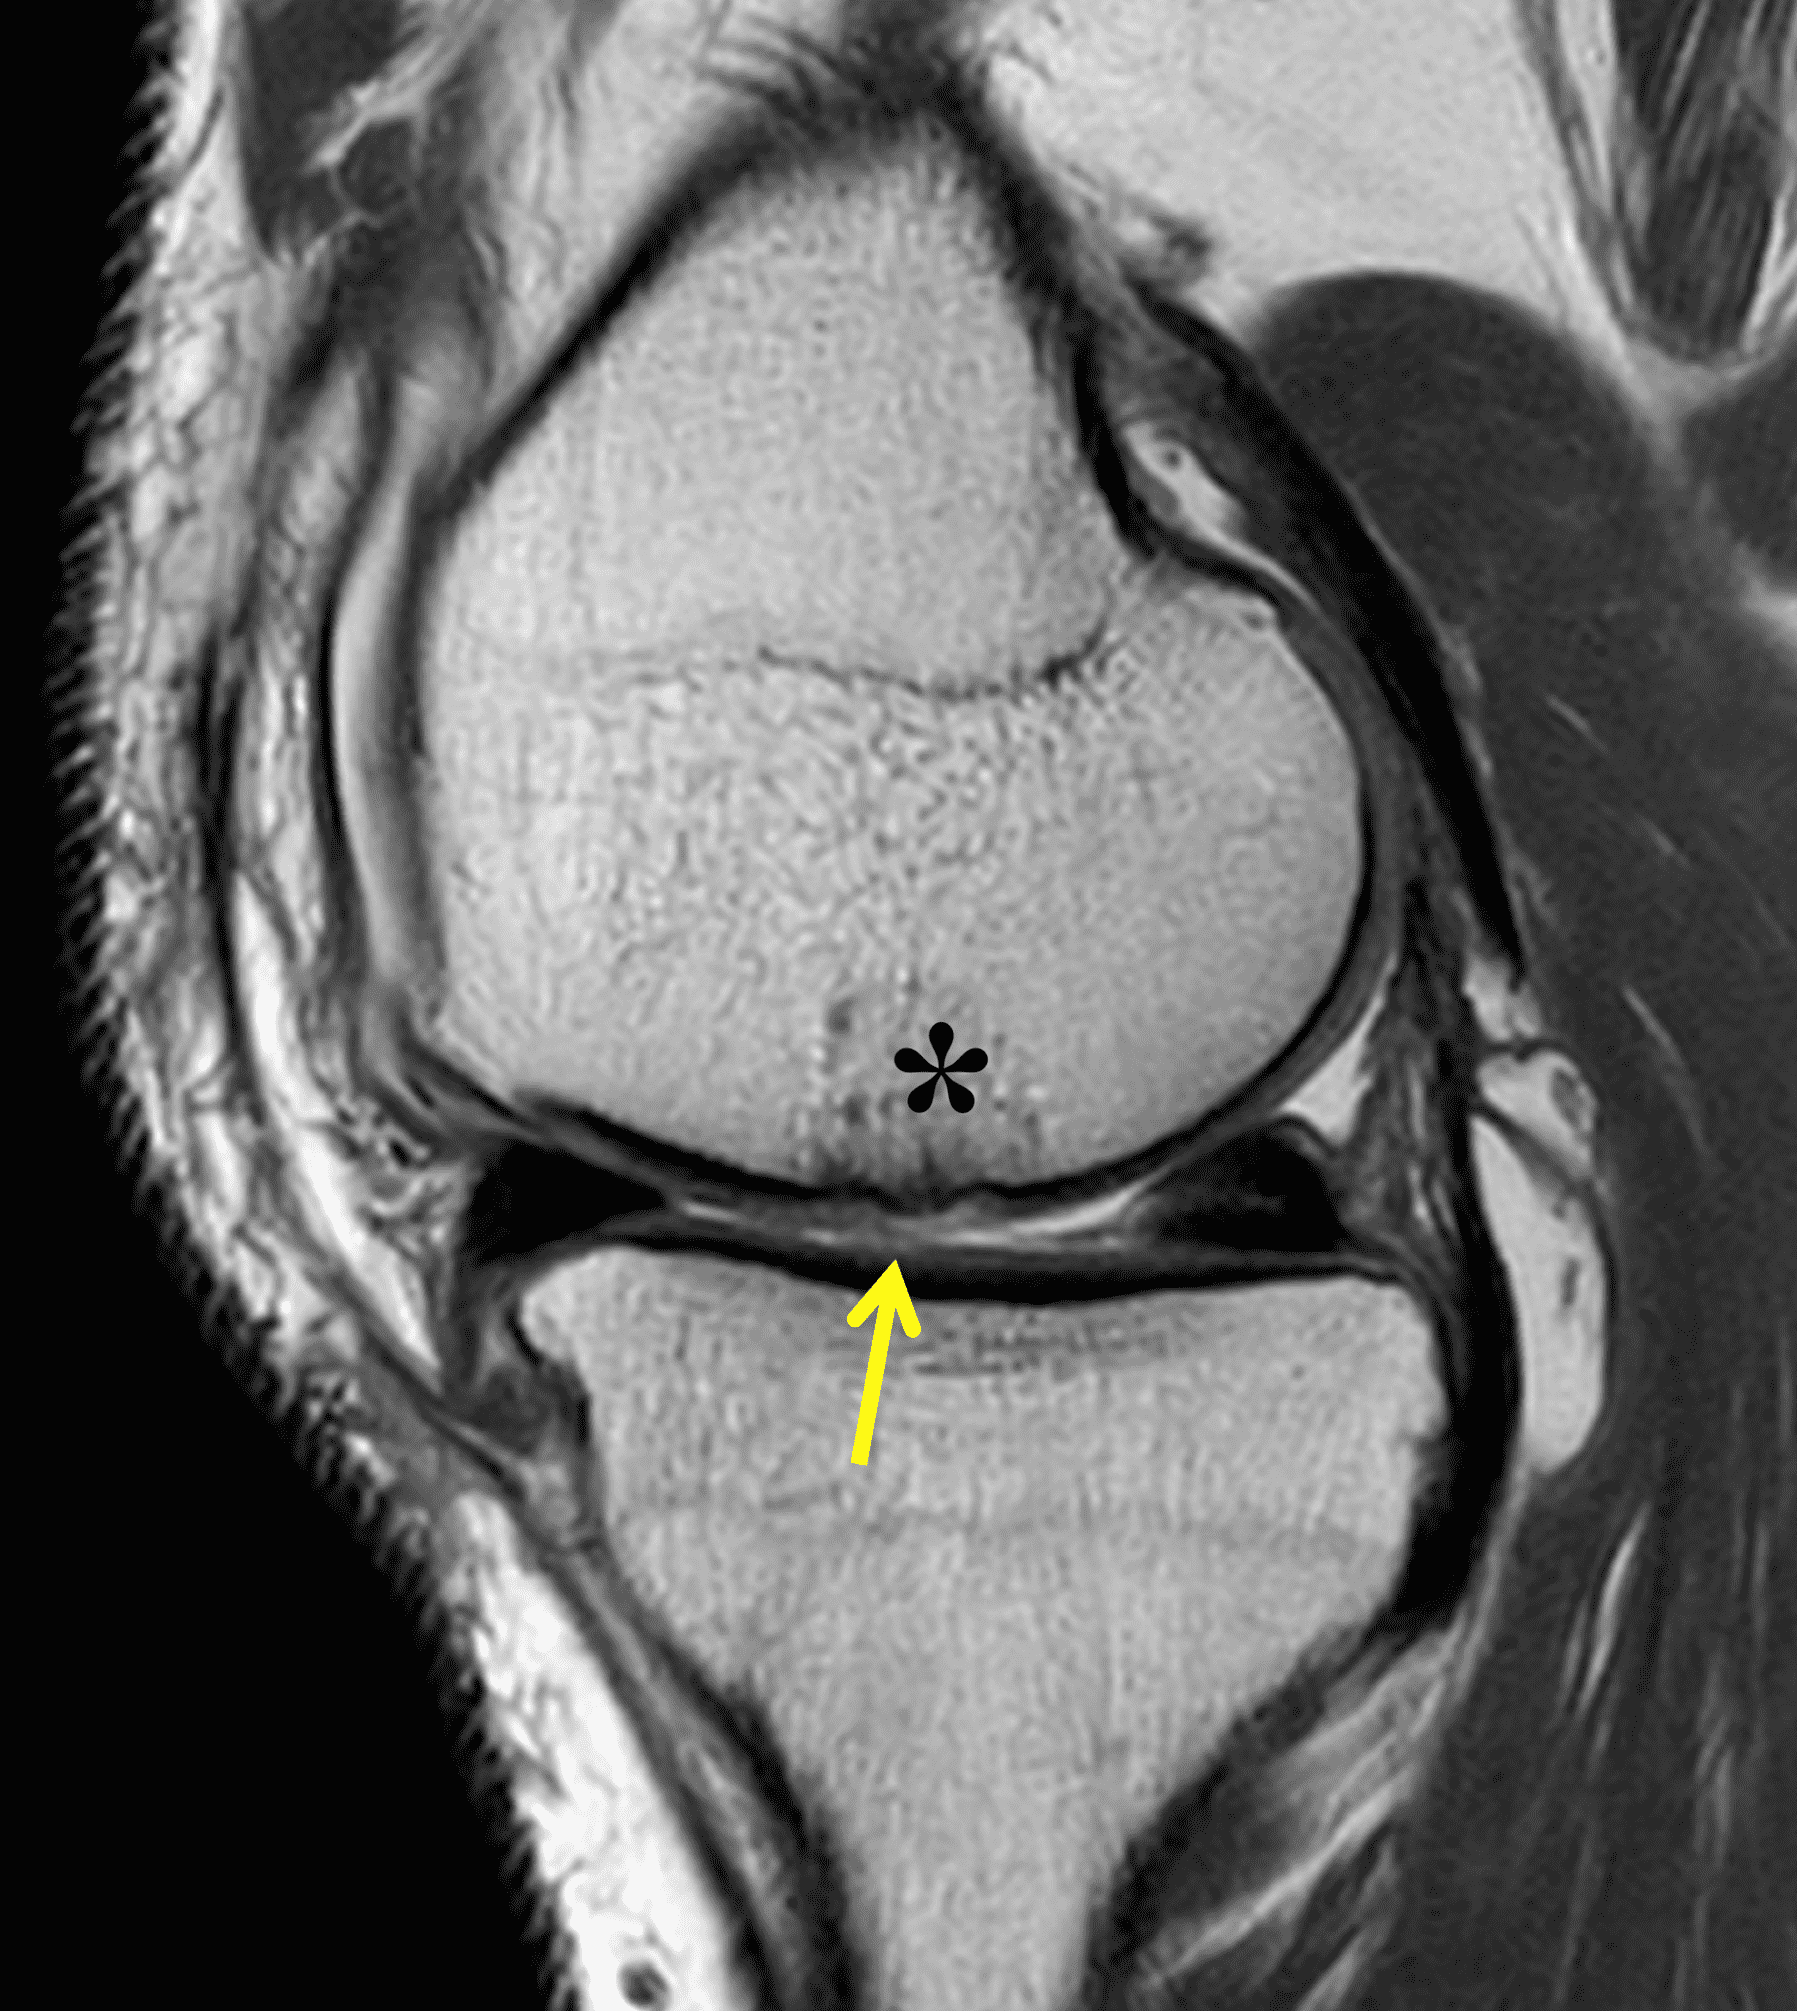

A 32-year-old man suffered a traumatic chondral injury to the medial femoral condyle that was treated with an osteochondral allograft 20 months previously. Representative images from a current knee MRI include (1A) coronal fat-suppressed fluid-sensitive and sagittal (1B) T1-weighted, (1C) proton density-weighted, and (1D) T2-weighted sequences. Are the post-operative MRI findings normal and expected, or abnormal and pathologic? Based on these images, would you characterize the procedure as a success or failure?

Figure 2: (2A) On the coronal image, the margins of the osteochondral graft are faintly visible (arrowheads). Both the graft and underlying bone show mild marrow edema, an expected finding. (2B) The T1-weighted image shows continuity of the marrow in the graft (asterisks) with the underlying bone, indicating osseous integration. A bioabsorbable pin (arrow) used for graft fixation is partly visible. (2C) The proton density-weighted image shows a low signal intensity seam (black arrow) between the native cartilage and transplant, as well as a defect in the subchondral bone plate of the graft (red arrow) where the pin was drilled, both normal findings. (2D) The T2-weighted image shows a smooth, congruent articular surface (arrows), restoring the normal anatomy, and a tiny subchondral cyst. No findings are present to suggest graft failure. The patient’s current symptoms were attributed to pathology elsewhere in the joint (not shown).

Successful osteochondral allograft procedure.

The postoperative imaging appearance of osteochondral allografts is similar to autografts (Figure 2).33 The subchondral bone plate of the donor and recipient sites do not have to match, but the articular surface should be congruent. Grafts that fail to incorporate by one year have a poor prognosis. Persistent marrow edema (beyond 12 months), a thick graft interface containing cysts or fluid, and subsidence of the graft are associated with poor osseous healing and worse outcomes. Extensive host marrow edema and severe synovitis may be a clue to immunologic rejection of the graft (Figure 18).21, 34